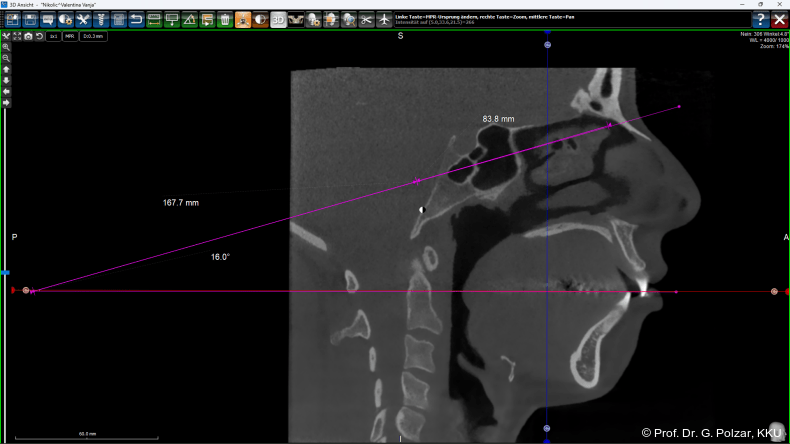

Die zu bildende Fläche (CranioPlan) wird nun auf den Mittelpunkt der Bipupillarlinie zentriert. Verlängert man diese Fläche um das Drei­fache nach dorsal und verbindet das hintere Ende mit der Okklusionsebene, so erhält man einen Winkel, der dem Winkel der Frankfurter Horizontale (Orbitalpunkt/Tragionslinie) mit der Okklusionsebene entspricht. Da diese Grundlinie der Frankfurter Horizontalen nicht so genau bestimmt werden kann, sind die Bezugswerte der CranioPlan-Analyse wesentlich genauer und auch leichter reproduzierbar (Abb. 25).

Nach Lehmann et al. beträgt der Winkel der Frankfurter Horizontalen zur Camperschen Ebene (früher gleichgesetzt mit der Okklusionsebene) 10°bis 15°. Vertikale Gesichtstypen und flache asiatische Schädelformen haben einen höheren Wert, horizontale Gesichtstypen einen eher flacheren Winkel. Nach Untersuchungen von Slavicek 1984 beträgt die Abweichung der Camperschen Ebene von der Okklusionsebene nach dorsal jedoch ca. 8°. Das heißt bei genauerer Betrachtung müsste man einen Winkel von 2° bis 7° zwischen CranioPlan-Ebene und Okklusionsebene mit einer Streuung von ca. 6° als Normwert bezeichnen.

Im Idealfall wäre dann bei der vorgestellten Patientin ein Wert von 13° als vertikaler Typ noch akzeptabel (Abb. 26). Vor der bimaxillären Umstellungsosteotomie kippt die Okklusionsebene nach links cranial (Abb. 27a+b).